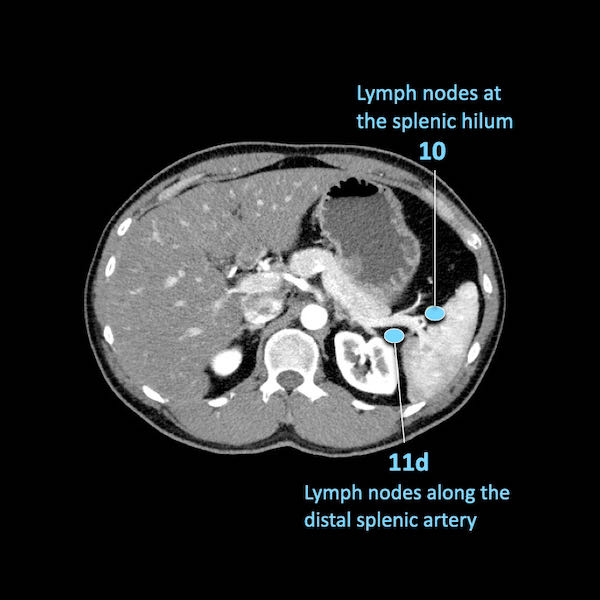

Điều quan trọng là phân biệt giữa hạch bạch huyết vùng và hạch bạch huyết ngoài vùng (di căn xa).

Các vị trí ngoài vùng chính là cạnh động mạch chủ và bên trái SMA.

Các hạch nghi ngờ ở những vị trí này cần được ghi nhận và sinh thiết.

Trong hình minh họa này, chúng tôi sử dụng các trạm hạch bạch huyết trong ung thư tụy theo đề xuất của Hội Tụy học Nhật Bản.

Danh sách đầy đủ được cung cấp trong chương về báo cáo. Nhấn vào đây.

Di căn hạch bạch huyết là yếu tố tiên lượng quan trọng và xảy ra ở khoảng hai phần ba bệnh nhân ung thư tụy có khả năng cắt bỏ.